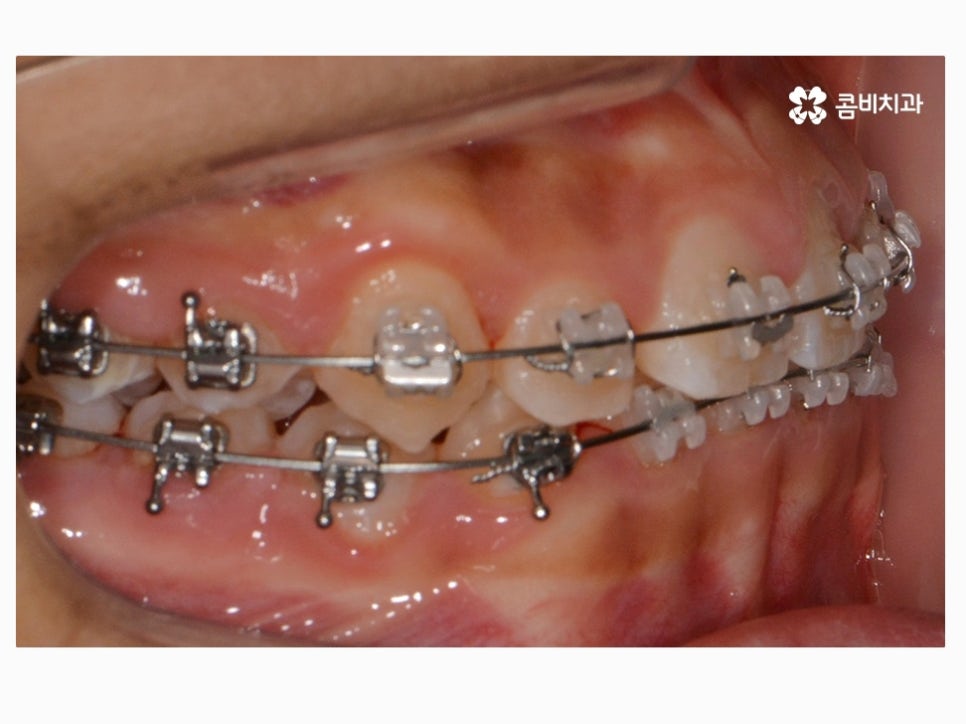

부정교합을 치료하는 방법은 나이대와 어떤 상태인지 진단에

따라서 달라질 수 있는데 위 케이스처럼 일반적인 치아교정으로

진행이 되는 경우도 있고 구외 교정 장치를 활용하는 경우 등 진단에 따라 다양할 수 있어요.

위 환자분께서 사용하신 장치는 클리피씨로 자가 결찰 장치이며

초기 통증이 줄어들고 관리가 용이하며 시술 기간을 단축시킬 수 있다는 장점이 있어요.

요즘은 이처럼 세라믹 재질을 활용하여 심미성은 높이고

교정 과정이 보다 효율적인 장치가 많이 사용되고 있는데요.